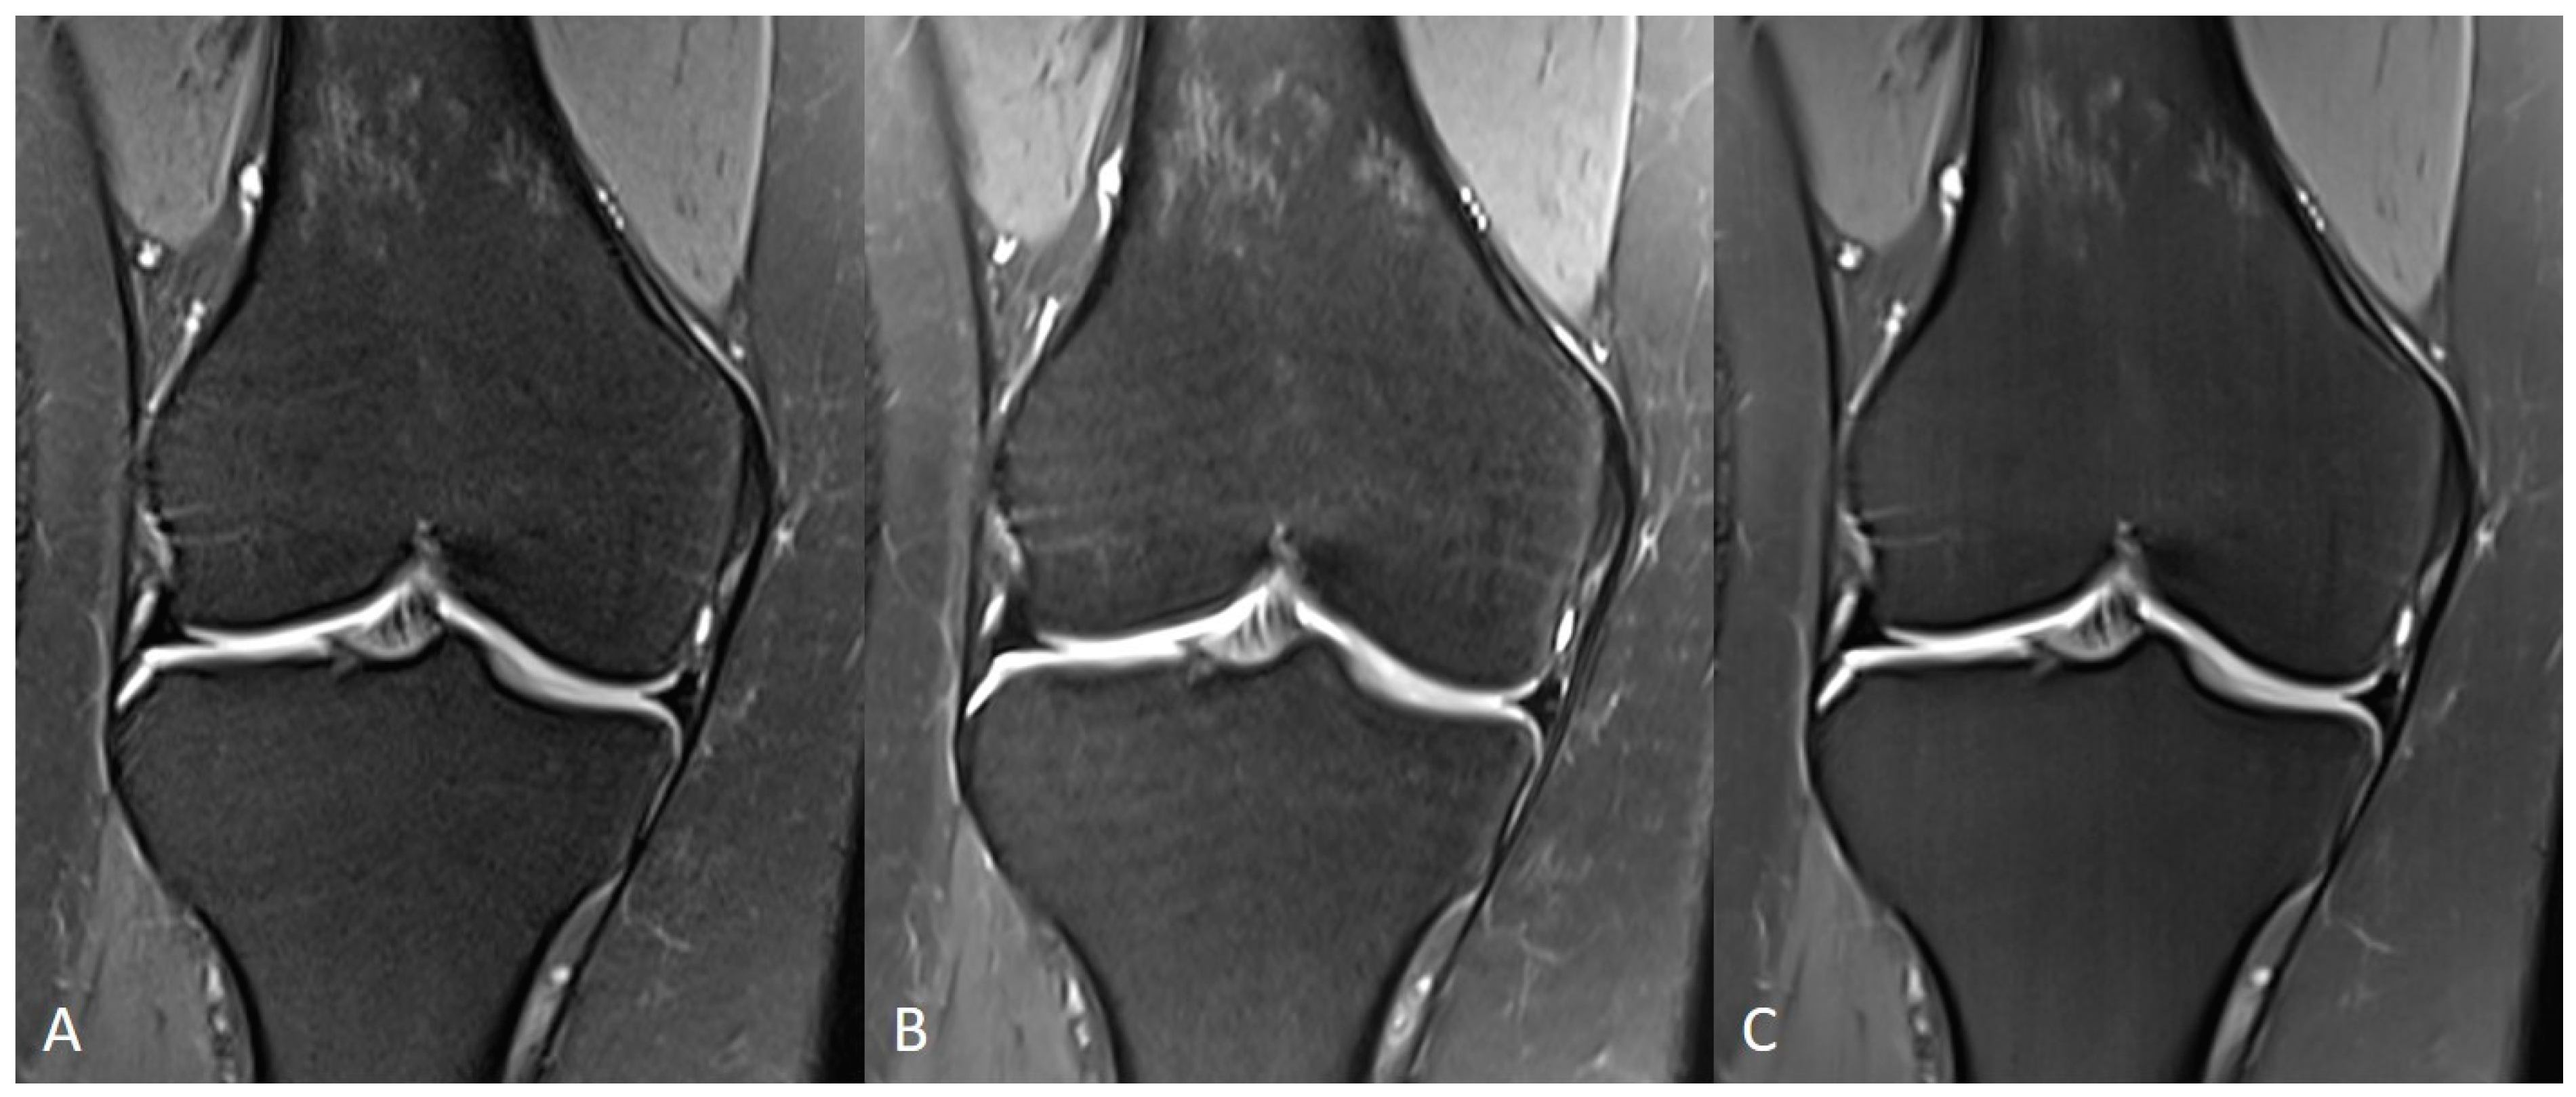

3.1. Assessment of Image Quality

3.2. Assessment of Anatomical Structures